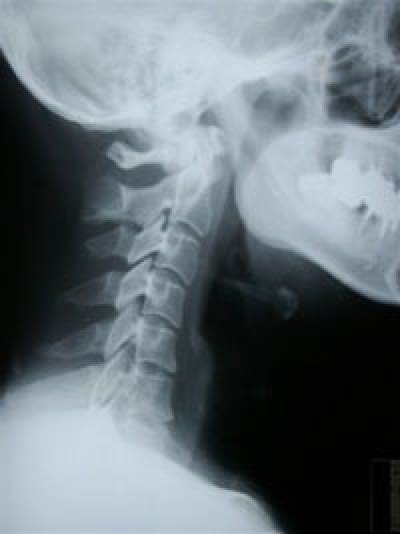

むち打ち(頚部捻挫)は交通事故による後遺症としては高い比率で発生します。

むち打ちとは、交通事故で車で追突された場合、体が前に押し出され、頭だけが残り首がむちがしなるような状態になるので「むち打ち」と呼ばれています。症状は首から肩にかけての痛み、頭痛・吐き気・めまいなどです。原因としては追突された際、頸椎(首)・胸椎(背部)・腰椎に外力が加わり、その関節が持つ運動範囲以上の動きを強制される事により、筋肉や靭帯、関節包などに損傷を惹き起こした状態です。 むちうち症と診断されるものの、ほとんどがこの頸部捻挫型と考えられています。

不意に強い衝撃をうけると関節が引っかかって動きが悪くなり炎症がおこり腫れてきます。ですから、病院でX-Pをとっても骨には異常が見つかりませんし、痛みの原因がわかりません。